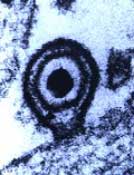

Dieses Beispiel zeigt einen der seltenen Fälle von Mononukleose, die primär als akute Hepatitis mit Ikterus ohne Pharyngitis, Lymphadenopathie oder andere Symptome imponieren.

Es sind IgG und IgM - Antikörper gegen "early antigen" vorhanden bei gleichzeitig (noch) negativen Antikörpern gegen "Epstein-Barr nuclear antigen 1" (EBNA-1). Dies ist typisch für eine kürzlich erworbene EBV-Infektion.

Wichtige Hinweise auf eine infektiöse Mononukleose findet man im Differenzialblutbild in Form der deutlichen Lymphozytose mit den atypischen Lymphozyten. Auch der wenig sensitive "Mononukleose Schnelltest", der seit diesem Jahr nicht mehr zu den kassenpflichtigen Laborleistungen gehört, erlaubt (wenn er positiv ist) bei passender Klinik, jungem Alter des Patienten und einem kompatiblen Blutbild die "kostengünstige" Diagnose einer infektiösen Mononukleose. Im vorliegenden Fall jedoch verzichtete der Hausarzt sowohl auf das Blutbild wie auch auf eine EBV-Serologie, weil die typischen Symptome einer Mononukleose fehlten. Dies führte etwas ins "diagnostische Abseits", was aber für den Patienten – retrospektiv gesehen - kaum von Nachteil war. |